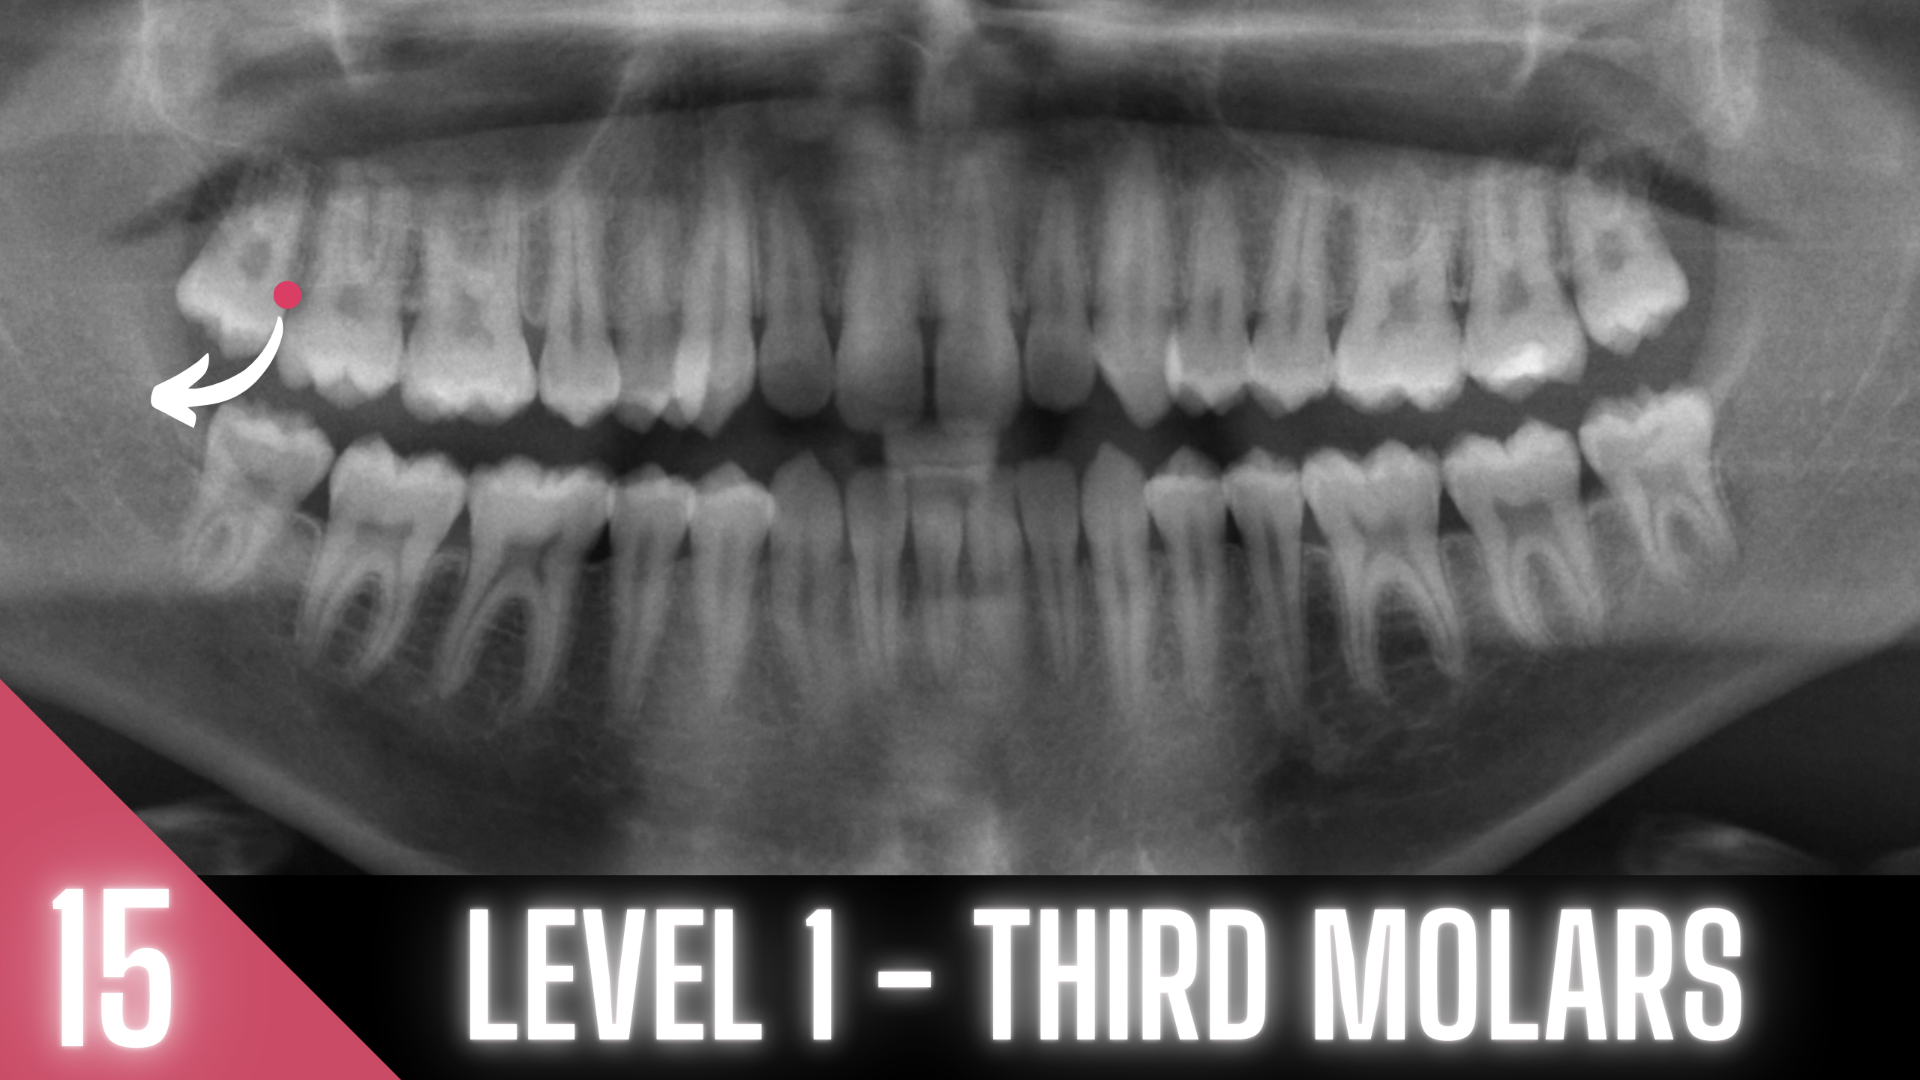

20 MODULES TO MASTER EXODONTIA

Everything you will ever need to know to master exodontia!